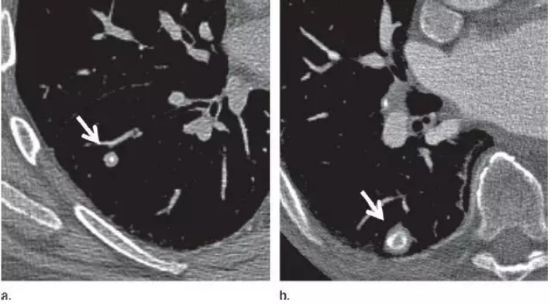

在中国人的印象里 心和肺一直是“形影不离”的 海尔兄弟 成语里有 撕心裂肺 狼心狗肺 没心没肺 …… 医学术语里有 心肺功能 心肺复苏 心肺康复 …… 尤其是当肺部查出“小阴影” 心更是脱不了关系 每天都惴惴不安 今天肿医君就来带大家看看 这让人烦恼的 肺部结节 Part.1: 肺部结节 真实病例: 张阿姨今年48岁,单位体检结果显示,肺上有一个0.8cm的小结节。张阿姨听说肺结节会变成肺癌,她担心极了,让儿子帮忙上网查询,向其他人咨询,可她得到的建议多种多样,让刘阿姨无所适从。 慢慢长大会不会变成肺癌啊 肺癌是世界上发病率及死亡率最高的恶性肿瘤,也是我国发病率和死亡率最高的疾病。目前约 75% 的肺癌患者在诊断时已属晚期,5年生存率仅为 15.6%。提高肺癌生存率的唯一途径是端口前移,早发现、早诊断和早治疗。 美国《化学文摘》2018全球癌症统计报告显示 肺癌(蓝色)高居发病率和死亡率之首 全球发病率11.6% 全球死亡率18.4% 湖南省肿瘤医院胸外一科 主任医师 陈跃军 很多患者忧心忡忡,不知道是否该进行进一步检查。如果对体检报告中的一些疾病迹象置若罔闻,等“小结节”长大变成了“肿块”,往往已错过最佳手术时机。那么我们应该怎么正确对待肺部结节呢? Part.2: 结节的分类 知识点 肺部结节(solitary pulmonary nodule,简称SPN)是肺实质完全包围的单发小病灶,类圆形或不规则形状,通常边界清晰,由肺实质包裹,不累及肺门和胸腔纵隔胸膜,不引发肺炎、肺不张或胸腔积液的组织。 肺结节分类如下 按大小: 肺结节中,直径1cm以内的称为小结节,直径0.5cm以内为微结节。局部病灶直径>3cm者称为肺肿块,也有医院将其报告为肺肿物或肺占位。 肺部结节尺寸越大,肺癌的可能性相对较大。 按数量: 肺结节可以是孤立性或多发性,孤立性肺结节即单个病灶,多无明显症状,属于边界清楚、密度增高且周围被含气肺组织包绕的软组织影。2个及以上病灶称为多发性肺结节。 肺结节的个数与肺癌可能性没有相关性 按密度: 根据病灶密度不同,肺结节还可分为实性肺结节和亚实性(非实性)肺结节,后者包括纯磨玻璃样结节。实性肺结节是肺内局限的密度增高影,病变密度相对较高,掩盖其中走行的肺细小支气管影和血管影(肺纹理);纯磨玻璃结节指CT显示的肺内密度稍增高影,通过病灶仍然能看到肺纹理影,就像透过磨玻璃观察到相对模糊的影像一样。 磨玻璃样结节尤其是持续存在的磨玻璃样结节,一般是肿瘤性病变 湖南省肿瘤医院胸外一科 主任医师 陈跃军 发现肺结节之后,不用过分紧张,但也不能掉以轻心,大部分肺结节都是良性的,只有少数肺结节是恶性的。 Part.3: 区分结节性质 结节良性的三大表现 1、 结构清晰,边缘平滑。内含脂肪和钙化的实性结节(箭头),符合错构瘤表现。建议进一步 CT 随访。 源自美国Fleischner 学会2017 年公布案例图(下同) 2、 有明显钙化痕迹。CT 图像显示边界清楚的中心钙化(a)或层状钙化(b)结节,均为典型的肉芽肿表现。建议进一步 CT 随访。 3、没有变大的趋势,甚至逐渐消失。(a)左肺上叶层厚 1 mm 的 CT 横断面图像,显示一个模糊的 10 mm 大小磨玻璃样结节(箭头)。(b)4 个月后的 CT 随访图像,显示未经治疗的病变在随访间期消失,符合良性病因,如局灶性感染。 结节恶性的三大表现 1、 毛刺状结节 左肺上叶层厚 1 mm 的 CT 横断面图像,显示一个可疑的实性毛刺状结节(箭头)。手术证实为浸润性腺癌。 2、 磨玻璃区域逐渐长大的结节 (a)右肺中部层厚 1 mm 的 CT 横断面图像,显示一个 10 mm 大小的纯磨玻璃样结节(箭头)。(b)同一位置 15 个月后的 CT 随访图像,显示病变的不透明度只有很小增加。(c)取得 b 图 10 个月后,同一位置的 CT 图像,显示结节已发展成较大的实性结节。手术切除证实为 1A 期浸润性鳞屑样为主的腺癌 3、实性结节逐渐变大的结节 (a)右肺下叶上段层厚 1 mm 的 CT 横断面图像,显示一个高度可疑(较大、磨玻璃样外观和实性形态)的部分实性结节(箭头)。(b)3 个月后的 CT 随访图像显示,实性成分的大小逐渐增加。手术显示为浸润性腺癌。 除了上述影像资料,咨询者的生活方式也是判断依据。 肺癌的高危人群 (1)年龄在55岁以上; (2)年数乘以每天吸烟的支数>400支*年的吸烟患者,其中也包括曾经吸烟,但戒烟时间不足15年者;被动吸烟者; (3)有职业暴露史(石棉、铍、铀、氡等接触者); (4)有恶性肿瘤病史或肺癌家族史; (5)有慢性阻塞性肺疾病(COPD)或弥漫性肺纤维化病史。 Part.4: 发现结节怎么做? 1、肺部小结节并不等于肺癌,并且大部分是良性的,有的通过保守治疗如抗炎或抗痨治疗,甚至不做任何治疗观察后消失。因为人体有自身免疫力的,只要营养好,一般的炎性病变可自行吸收。 2、当医生判断结节恶性可能性较小时,还是建议患者要定期检查胸部CT。5毫米以下的微结节每年复查一次,5至10毫米的小结节每三个月复查一次,随访三至五年。 CT在肺内病变中的诊断优势非常明显,CT通过显示组织横断面及三维结构图像进行诊查,有效避免了肺与心脏、纵隔、横膈等组织的重叠,能发现肺尖、脊柱旁、靠近胸膜、心脏后方等部位胸片难以发现的病灶。另外,低剂量CT筛查所产生的射线剂量很低,对人体的影响极低。 3、当医生判断为恶性可能性较大时,应早期进行手术(胸腔镜)治疗。国内外多个研究结果显示,经过手术治疗的I期患者的10年生存率达到了90%以上。 目前微创胸腔镜手术是治疗肺部小结节、早期肺癌的主要方法。胸腔镜手术应用广泛,只需一个1cm胸腔镜观察孔和一个2-3cm操作孔,行肺叶或肺段切除术,疗效明确,创伤非常小,疼痛轻,术后恢复快,不需要做任何的化疗和放疗。 在我们临床工作中对上千例磨玻璃结节、微小结节患者的长期临床观察研究结果显示,90%以上患者的结节没有发生变化,10%的患者在随访过程中发现结节长大或实质成分增加等改变,及时手术,但没有一例出现复发转移,所以只要找对了专家,定期随访,并不会耽误治疗。 最危险的情况其实是病人发现肺部结节去看医生,医生考虑肺部小结节可暂时不处理,建议定期复查,而病人把不手术、不服药误认为没病,一直拖到出现症状后再去就诊,耽误了病情。